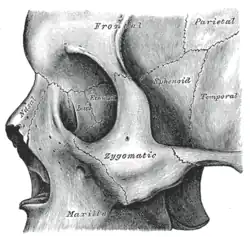

Close-up.

Close-up. -